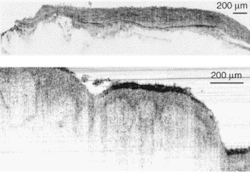

Recently, Wolfgang Drexler and his colleagues at the University of Vienna (Vienna, Austria), along with researchers from MenloSystems (Martinsried, Germany), have tested a broad-spectrum fiber laser emitting at 1375 nm to achieve sub-2-µm-axial-resolution OCT in nontransparent biological tissues.1 This resolution represents a 25% increase in axial OCT resolution. The tissues were ex vivo samples from a human artery and skin, which were imaged through thin layers of water to prevent dehydration and to optimize the index matching (see Fig. 1).

Individual layers and membranes are clearly visible in the artery and skin samples. The researchers believe this shows that an OCT system based on such a stable, low-cost, compact fiber laser has great potential for in vivo OCT clinical studies. To reach this point, laser performance must be improved by smoothing the emission spectrum and increasing the system output power two- to fivefold. A fiber-based OCT system capable of supporting the broad spectral output of the fiber laser will also have to be developed.